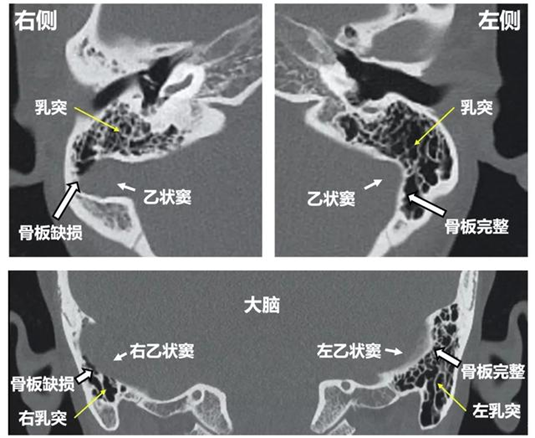

乙状窦:同样属于硬脑膜窦,与横窦紧密相连,形状类似乙字,故而得名。它也是重要的血液运输通道,接收横窦传来的血液,并将其进一步输送至颈内静脉,最终回流到心脏。乙状窦紧贴颞骨走行,与耳部结构关系密切。当乙状窦周围的骨质出现部分缺失或薄弱(称为骨壁缺损,图5)、或者乙状窦异常扩张形成小囊状结构(称为憩室,图6)等异常时,会使血流冲击和血管壁振动增强,产生异常声音,通过骨传导或气传导引发搏动性耳鸣。研究发现,乙状窦骨壁缺损在搏动性耳鸣患者中占有一定比例,是导致耳鸣的重要因素。

图5 乙状窦骨壁缺损的CT影像

像乙状窦这样重要的血管,如果它的骨板出现缺损,就如同道路的路基坏了一块。正常情况下,乙状窦就像一条平稳流淌的河流,血液安静地流动着。但骨板缺损后,血管壁失去了完整的支撑,变得 “脆弱” 起来。研究发现,乙状窦骨板缺损在搏动性耳鸣患者中占一定比例,有研究显示约22%的患者存在这种情况。而且,骨板缺损时,组织初阶振幅是正常人的1000倍以上。这就好比原本小声的水流声,因为河道破损,突然变成了大声的嘈杂声。血液流经这里,就像汽车经过坑洼路段,会产生剧烈颠簸,血管壁也跟着大幅振动,从而产生高声强的静脉声。这些声音就像被放进了一个 “声音放大器” 里,通过颞骨蜂房气腔这个 “传声筒”(图7),一路传到鼓室,最终被我们的耳朵捕捉到,变成了讨厌的搏动性耳鸣。